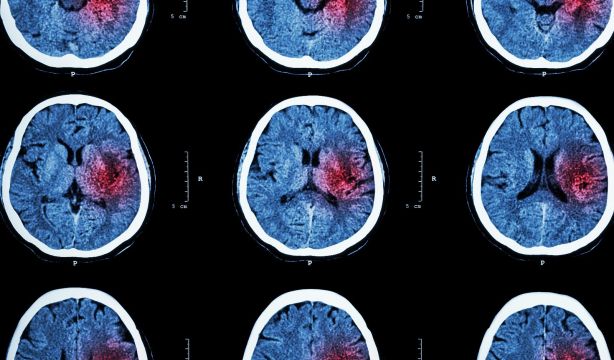

La anticoagulación es un tratamiento fundamental en la fibrilación auricular (FA) para reducir el riesgo sustancial de accidente cerebrovascular isquémico, que es 5 veces mayor en pacientes afectados en comparación con la población general, se recuerda en un trabajo de Circulation.

De hecho, cada año se dan casi 12 millones de casos de ictus y más de 7 millones de fallecimientos en todo el mundo por su causa. En España, anualmente se producen 90.000 nuevos casos de ictus y más de 23.000 fallecimientos, según la Sociedad Española de Neurología.